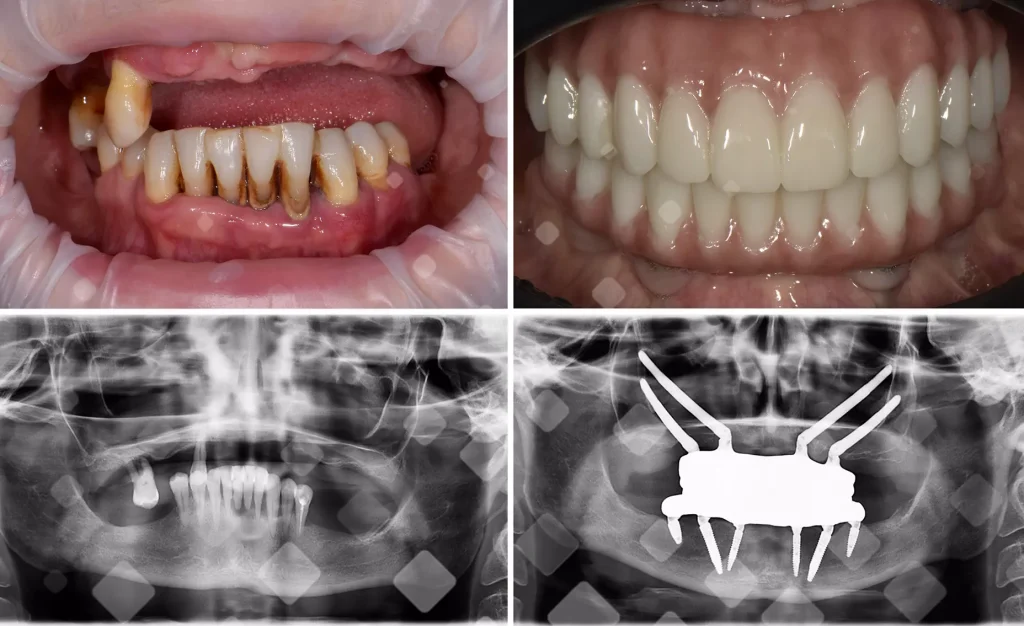

Кейс 2. «Болтается протез» — стабилизировали без повторной операции

Дмитрий, 42. Адаптационный протез на верхней челюсти «гулял». Сняли точные данные, спроектировали титановую балку и керамокомпозитный мост. Через 8 месяцев финализировали — с тех пор пациент ест яблоки без ножа.

«Я из Нижнего Новгорода: на верхней челюсти стоял “болтающийся” временный протез на имплантах — ел только мягкое. Отправил КТ и фото, мне спланировали лечение и помогли с поездкой. На месте сделали фотограмметрию, новую титановую балку и керамокомпозитный мост — посадка стала как перчатка. В тот же день откусил яблоко, а через месяц по видеосвязи только уточнили мелочи. Ценю, что поддержка не закончилась на двери клиники».

— Олег, 56 лет